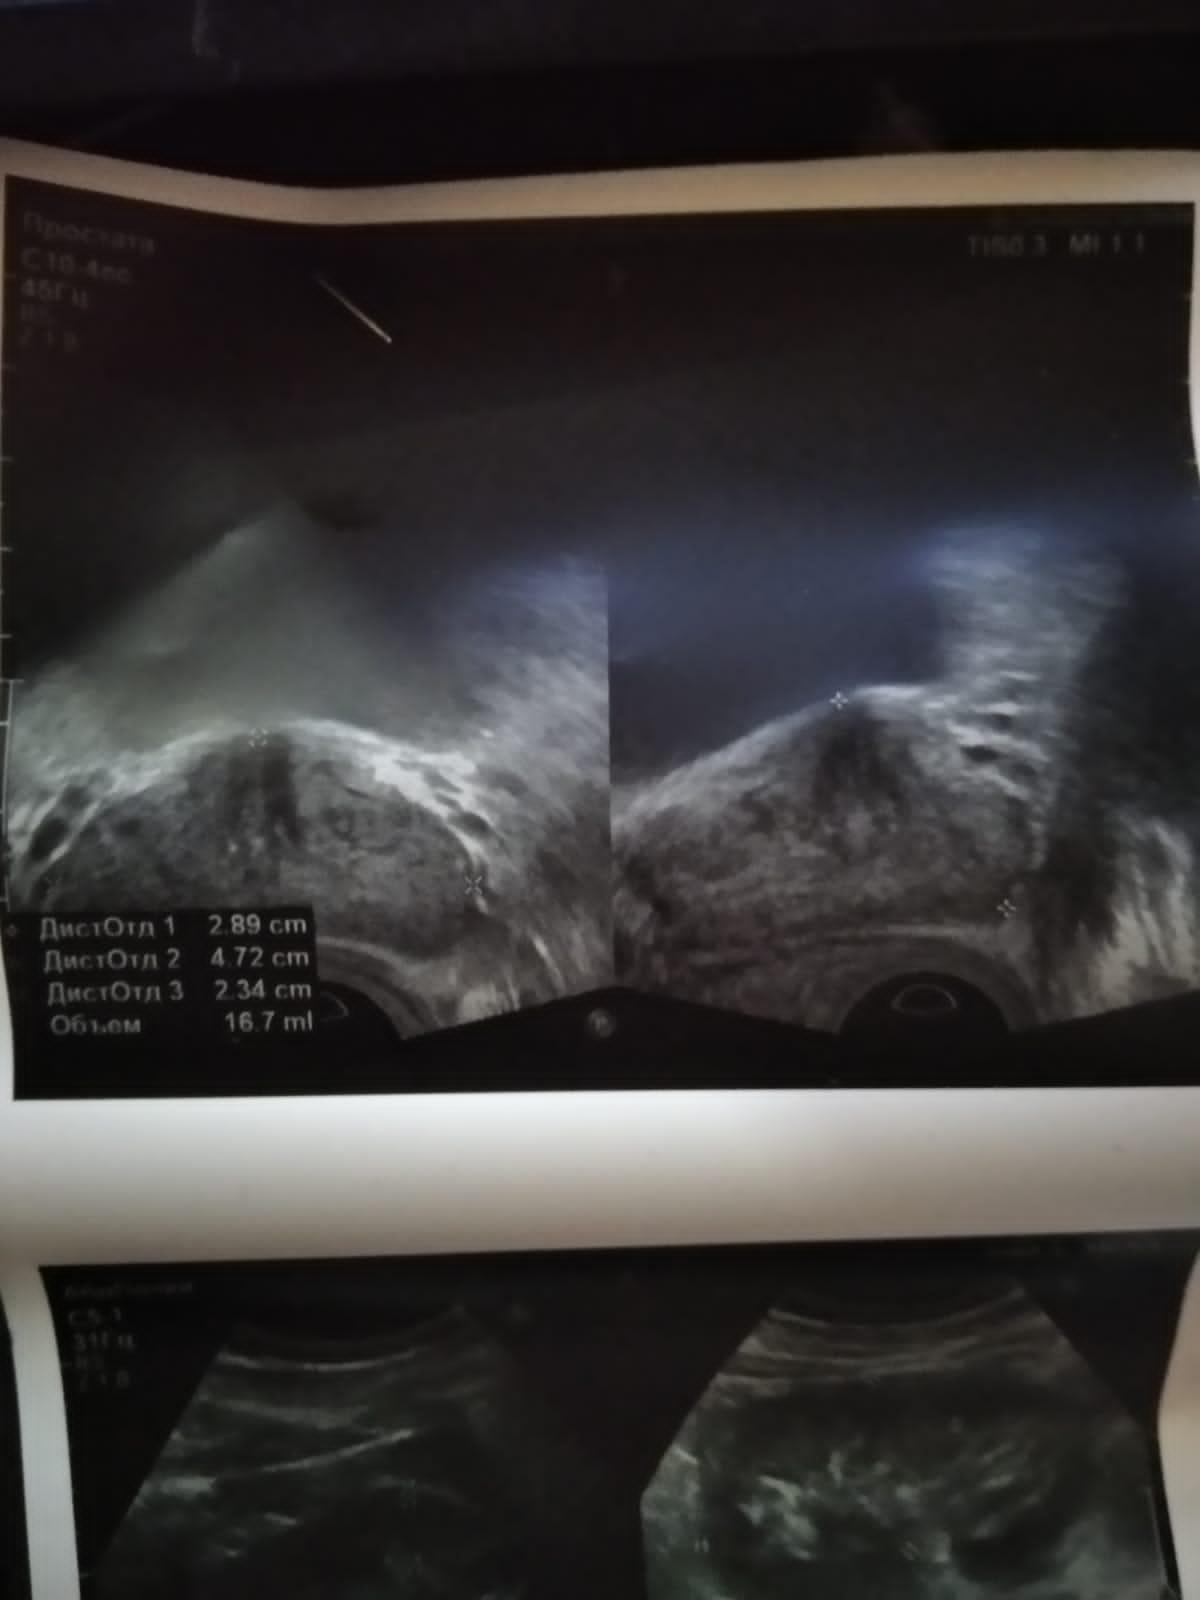

Делали УЗИ в поликлинике , сказали что кальцинаты и нужно делать массаж простаты, поставили диагноз хранический простатит, сделал трузи в платной клинике врач сказала что кальцинат не обнаружила, посмотрите пожалуйста фото трузи белые пятна это кальцинаты?

Здравствуйте! Оценивать визуализацию ультразвукового исследования можно только по ролику видео. По единичным фото можно лишь отметить ,что на представленных фото визуализируется предстательная железа и часть мочевого пузыря. На изображениях имеют место эхопозитивные и эхонегативные структуры. Результаты любого УЗИ оцениваются в совокупности с клиническими симптомами. Удачи!